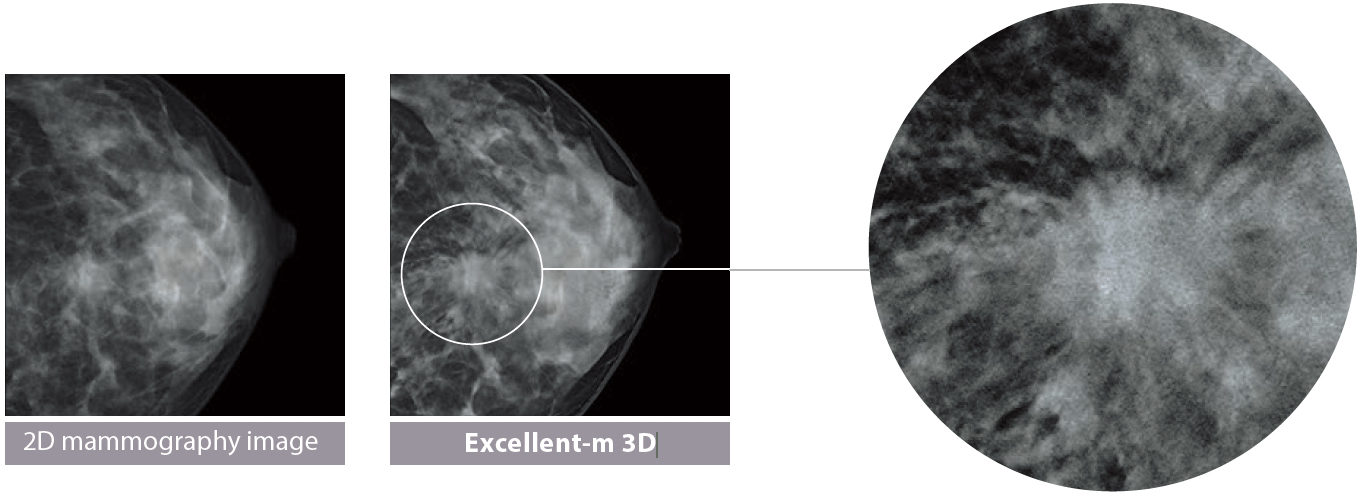

1. Reducing graininess of image in low-dose tomography

The image patterns are recognized to selectively suppress the patterns that do not exist in human body architectures as noise, to reduce distractive noises in the event of low-dose tomography.

2. Suppressing interference of human body architectures at different depths (as illustrated on the right)

In the process of reconstructing the 3D breast architecture from multiple 2D images, calcification, mass, spicula, mammary gland and other signals that emerge from different depths in the breast architecture are selected off to reproduce the breast architecture at the focus depth with greater fidelity.

3. Restoring the fine-structure

Our super-resolution technology is introduced to restore the fine-structure of calcification and other phenomena, the visibility of which is impaired by the movement of the X-ray tube, to facilitate interpretation of tomosynthesis images.